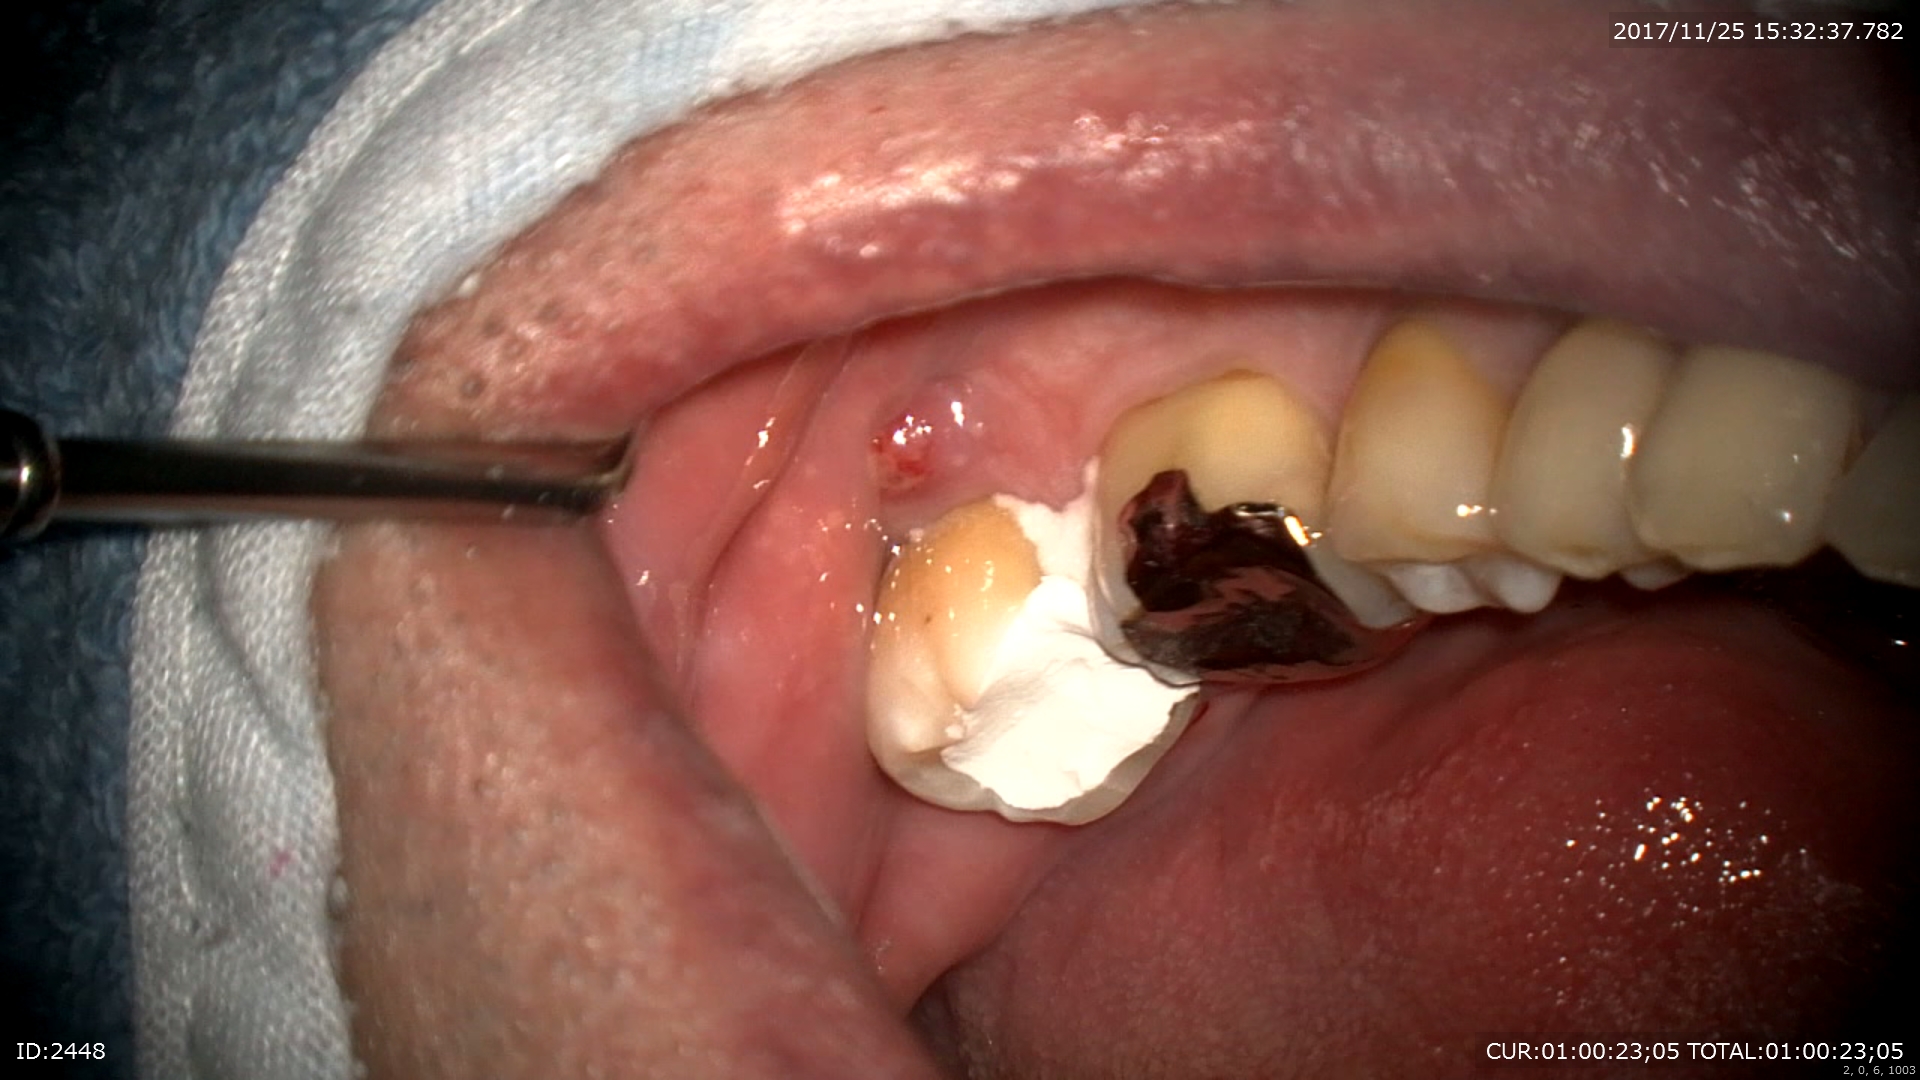

ケース1:マイクロエンド 主訴:歯茎が腫れた。口内炎?

ブログを見て頂いている方の中にもこのような症状ありませんか?今回のケースを見て頂くとご理解頂けると思いますが放っておいたら大変な事になる重症な病変でした。

いつも通りまず歯科ドックをして原因を調べます。ドックの結果神経が死んでいました。しかし今回わからなかったのは分岐部といって歯の又の部分にも病変がありました。。。

これはどう説明すれば。。。

CTとデンタルをみると髄床から何か管か破折線か見えます。なんだろう。これが分岐部病変の原因ではないかと思います。歯科ドックをしたからここまでわかりました。

さて丁寧に根管を探していきます。